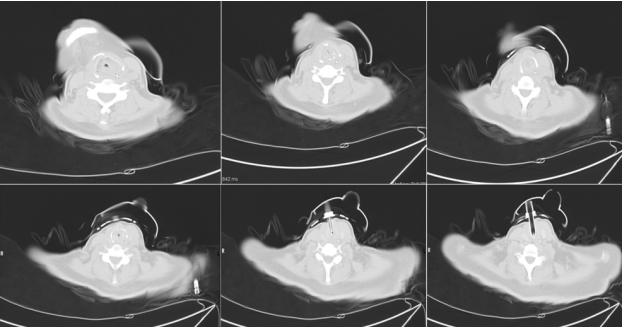

入院时颈部CT:整个气道大部分堵塞(图1)

图片

图1  患者入院时胸部CT